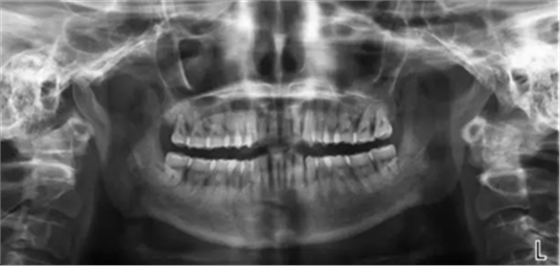

曲斷示:全口牙齒牙槽骨水平吸收根長(zhǎng)1/2-2/3。